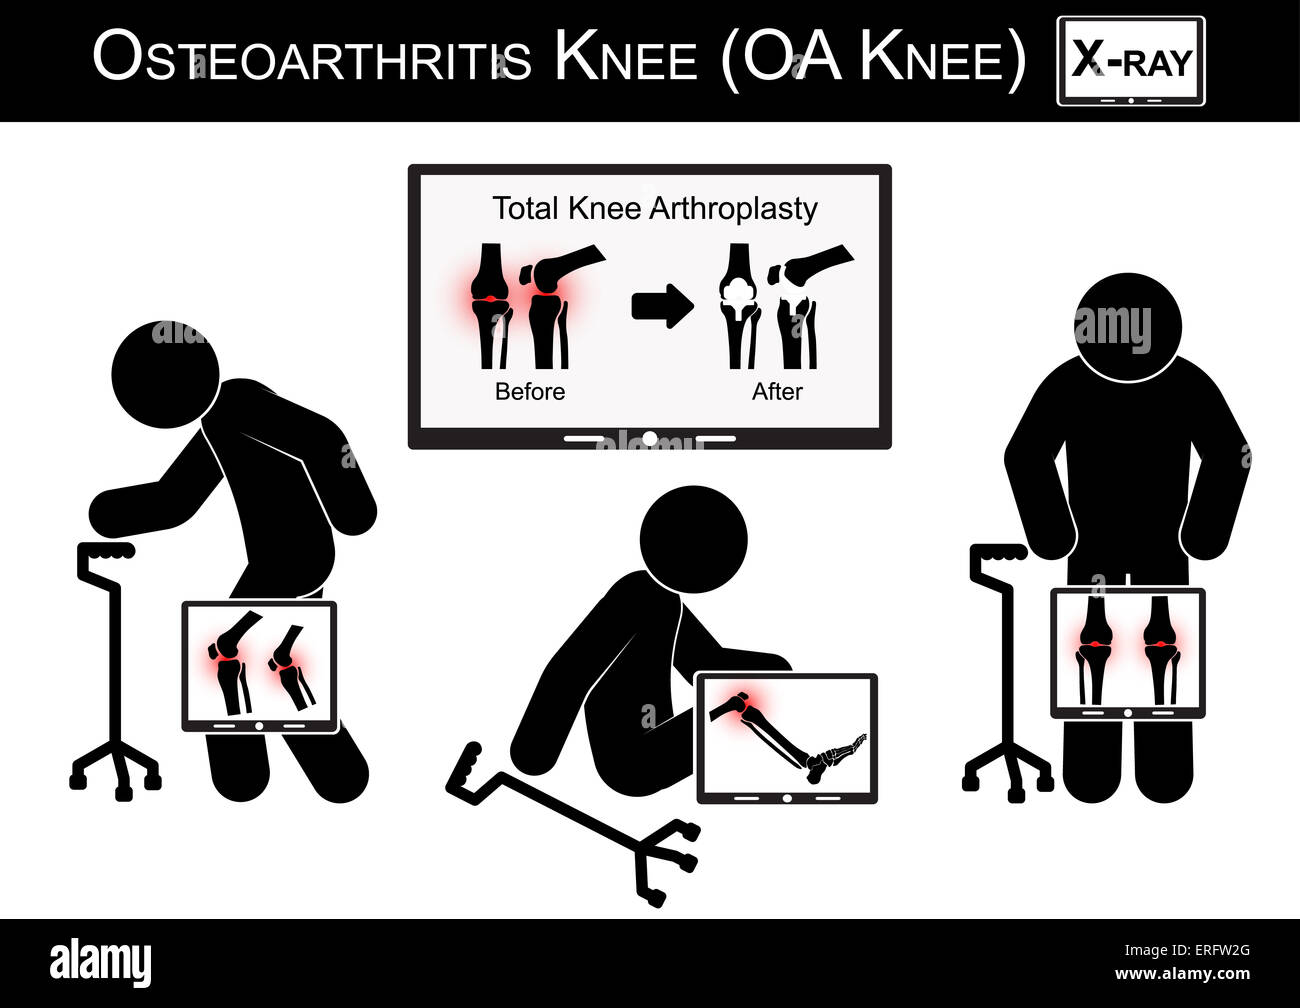

Vieil homme la douleur à son genou , Moniteur show image d'arthroplastie totale du genou ( avant et après traitement chirurgical de l'arthrose ) Banque D'Imageshttps://www.alamyimages.fr/image-license-details/?v=1https://www.alamyimages.fr/photo-image-vieil-homme-la-douleur-a-son-genou-moniteur-show-image-d-arthroplastie-totale-du-genou-avant-et-apres-traitement-chirurgical-de-l-arthrose-83327512.html

Vieil homme la douleur à son genou , Moniteur show image d'arthroplastie totale du genou ( avant et après traitement chirurgical de l'arthrose ) Banque D'Imageshttps://www.alamyimages.fr/image-license-details/?v=1https://www.alamyimages.fr/photo-image-vieil-homme-la-douleur-a-son-genou-moniteur-show-image-d-arthroplastie-totale-du-genou-avant-et-apres-traitement-chirurgical-de-l-arthrose-83327512.htmlRMERFW2G–Vieil homme la douleur à son genou , Moniteur show image d'arthroplastie totale du genou ( avant et après traitement chirurgical de l'arthrose )

Vieil homme la douleur à son genou , Moniteur show image d'arthroplastie totale du genou ( avant et après traitement chirurgical ) arthrose vector ( télévision des Illustration de Vecteurhttps://www.alamyimages.fr/image-license-details/?v=1https://www.alamyimages.fr/photo-image-vieil-homme-la-douleur-a-son-genou-moniteur-show-image-d-arthroplastie-totale-du-genou-avant-et-apres-traitement-chirurgical-arthrose-vector-television-des-133723002.html

Vieil homme la douleur à son genou , Moniteur show image d'arthroplastie totale du genou ( avant et après traitement chirurgical ) arthrose vector ( télévision des Illustration de Vecteurhttps://www.alamyimages.fr/image-license-details/?v=1https://www.alamyimages.fr/photo-image-vieil-homme-la-douleur-a-son-genou-moniteur-show-image-d-arthroplastie-totale-du-genou-avant-et-apres-traitement-chirurgical-arthrose-vector-television-des-133723002.htmlRFHNFH1E–Vieil homme la douleur à son genou , Moniteur show image d'arthroplastie totale du genou ( avant et après traitement chirurgical ) arthrose vector ( télévision des